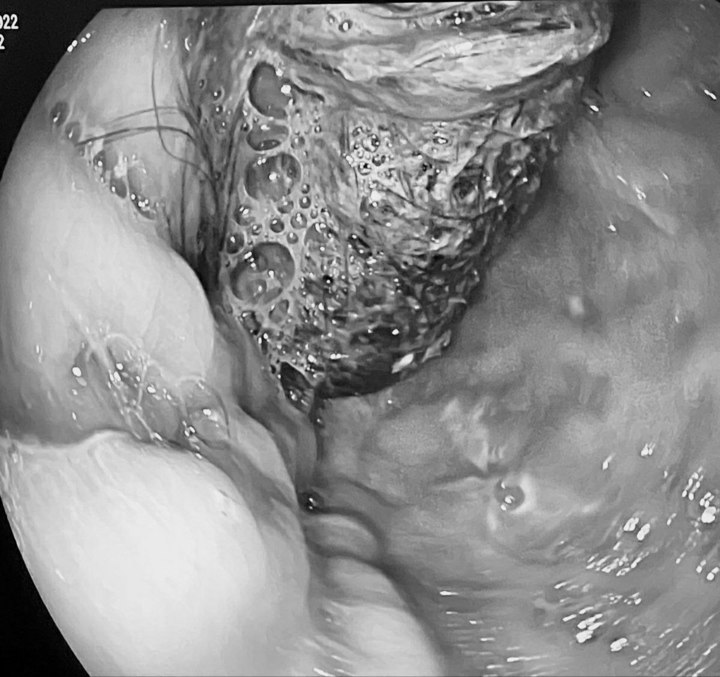

Как стало известно «МК», некоторое время назад в Детскую больницу №9 им. Сперанского поступила девочка с многократной рвотой и схваткообразными болями в животе. Ее госпитализировали с подозрением на острый гастрит. В разговоре с врачами юная пациентка призналась: за два дня до поступления в клинику она съела около двух рулонов туалетной бумаги. Ребенку выполнили ультразвуковое исследование брюшной полости, которое показало неожиданный результат. Специалисты обнаружили в желудке плотные образования округлой формы – ту самую съеденную бумагу, а кроме того – плотное образование из волос, так называемый трихобезоар размером 5 на 7 см. Трихобезоары могут образоваться, когда ребенок (или взрослый) имеет привычку грызть волосы. Попадая внутрь, они не перевариваются и со временем сбиваются в комок, который может разрастись так, что заполнит весь желудок.

Фото: t.me/speranskogo

Для «изгнания» из организма комков туалетной бумаги школьнице провели инфузионную терапию, а также поставили очистительные клизмы. Внушительный размер комка волос не позволял извлечь его эндоскопически, так же он не прошел бы через нижний отдел желудка. Здесь требовалось хирургическое вмешательство, поэтому детские хирурги выполнили так называемую гастротомию: создали искусственный вход в полость желудка через переднюю брюшную стенку и достали инородное тело.